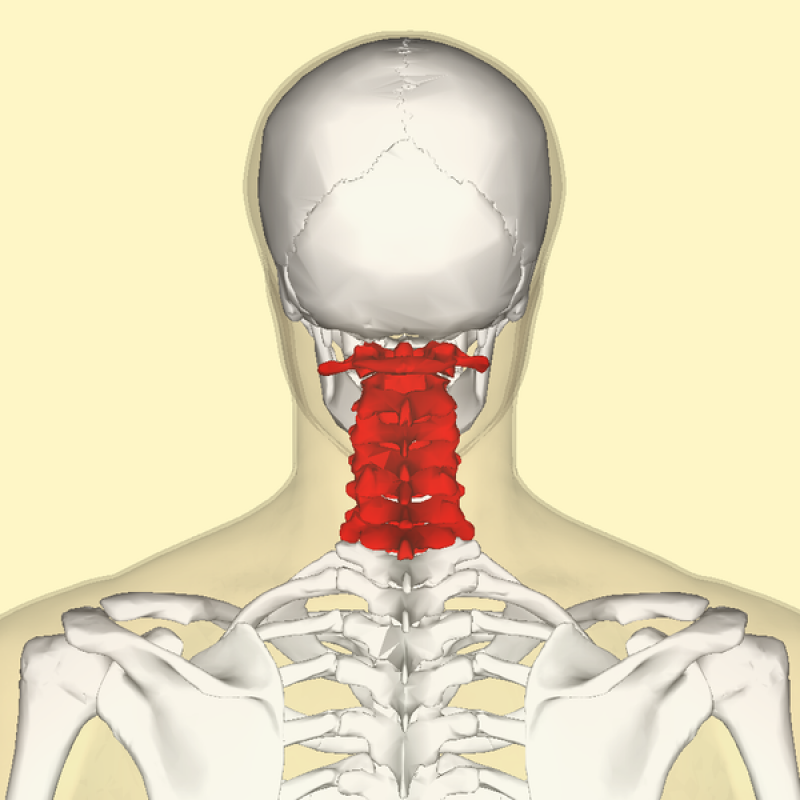

Exame de Imagem de Ressonância Magnética da Coluna Cervical

Exame de Imagem de Ressonância Magnética da Coluna Cervical

Exame de Imagem de Ressonância Magnética da Coluna Cervical

Medicom ExamesCom um exame de imagem é possível diagnosticar algum tipo de câncer e dessa forma seguir com um tratamento. Além do exame de imagem são feitos... Cotar Agora Saiba Mais